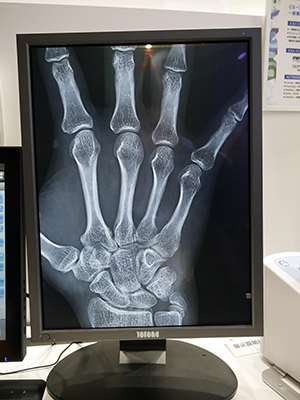

ブース内で注目を集めたのが,ワイヤレスタイプの可搬型DRのAeroDR fineである。日本国内で2011年4月に発表され,1万台以上出荷しているAeroDRの第三世代に位置づけられる。半切サイズ(14インチ×17インチ)FPDで,画素サイズ100μmとし,世界最高レベルの解像度を実現。従来のFPDよりもさらに高精細な画像を撮影できるようになった。これにより,整形領域の手指骨画像などで微細な病変を描出し,精度の高い診断を行える。高精細画像を必要としない検査では,データ量を増やさないように200μmに切り替えて撮影もできる。また,低被ばくでの撮影が可能なのもAeroDR fineの特長である。従来のAeroDRもX線光子検出効率と広いダイナミックレンジにより,フィルムやCRの約半分のX線照射量で高画質画像を得られていたが,AeroDR fineではCRと比べX線照射量を約62%低減。さらに低被ばく撮影が可能になった。

100μmの高精細画像を提供する「AeroDR fine」

「AeroDR fine」の手指骨画像 |